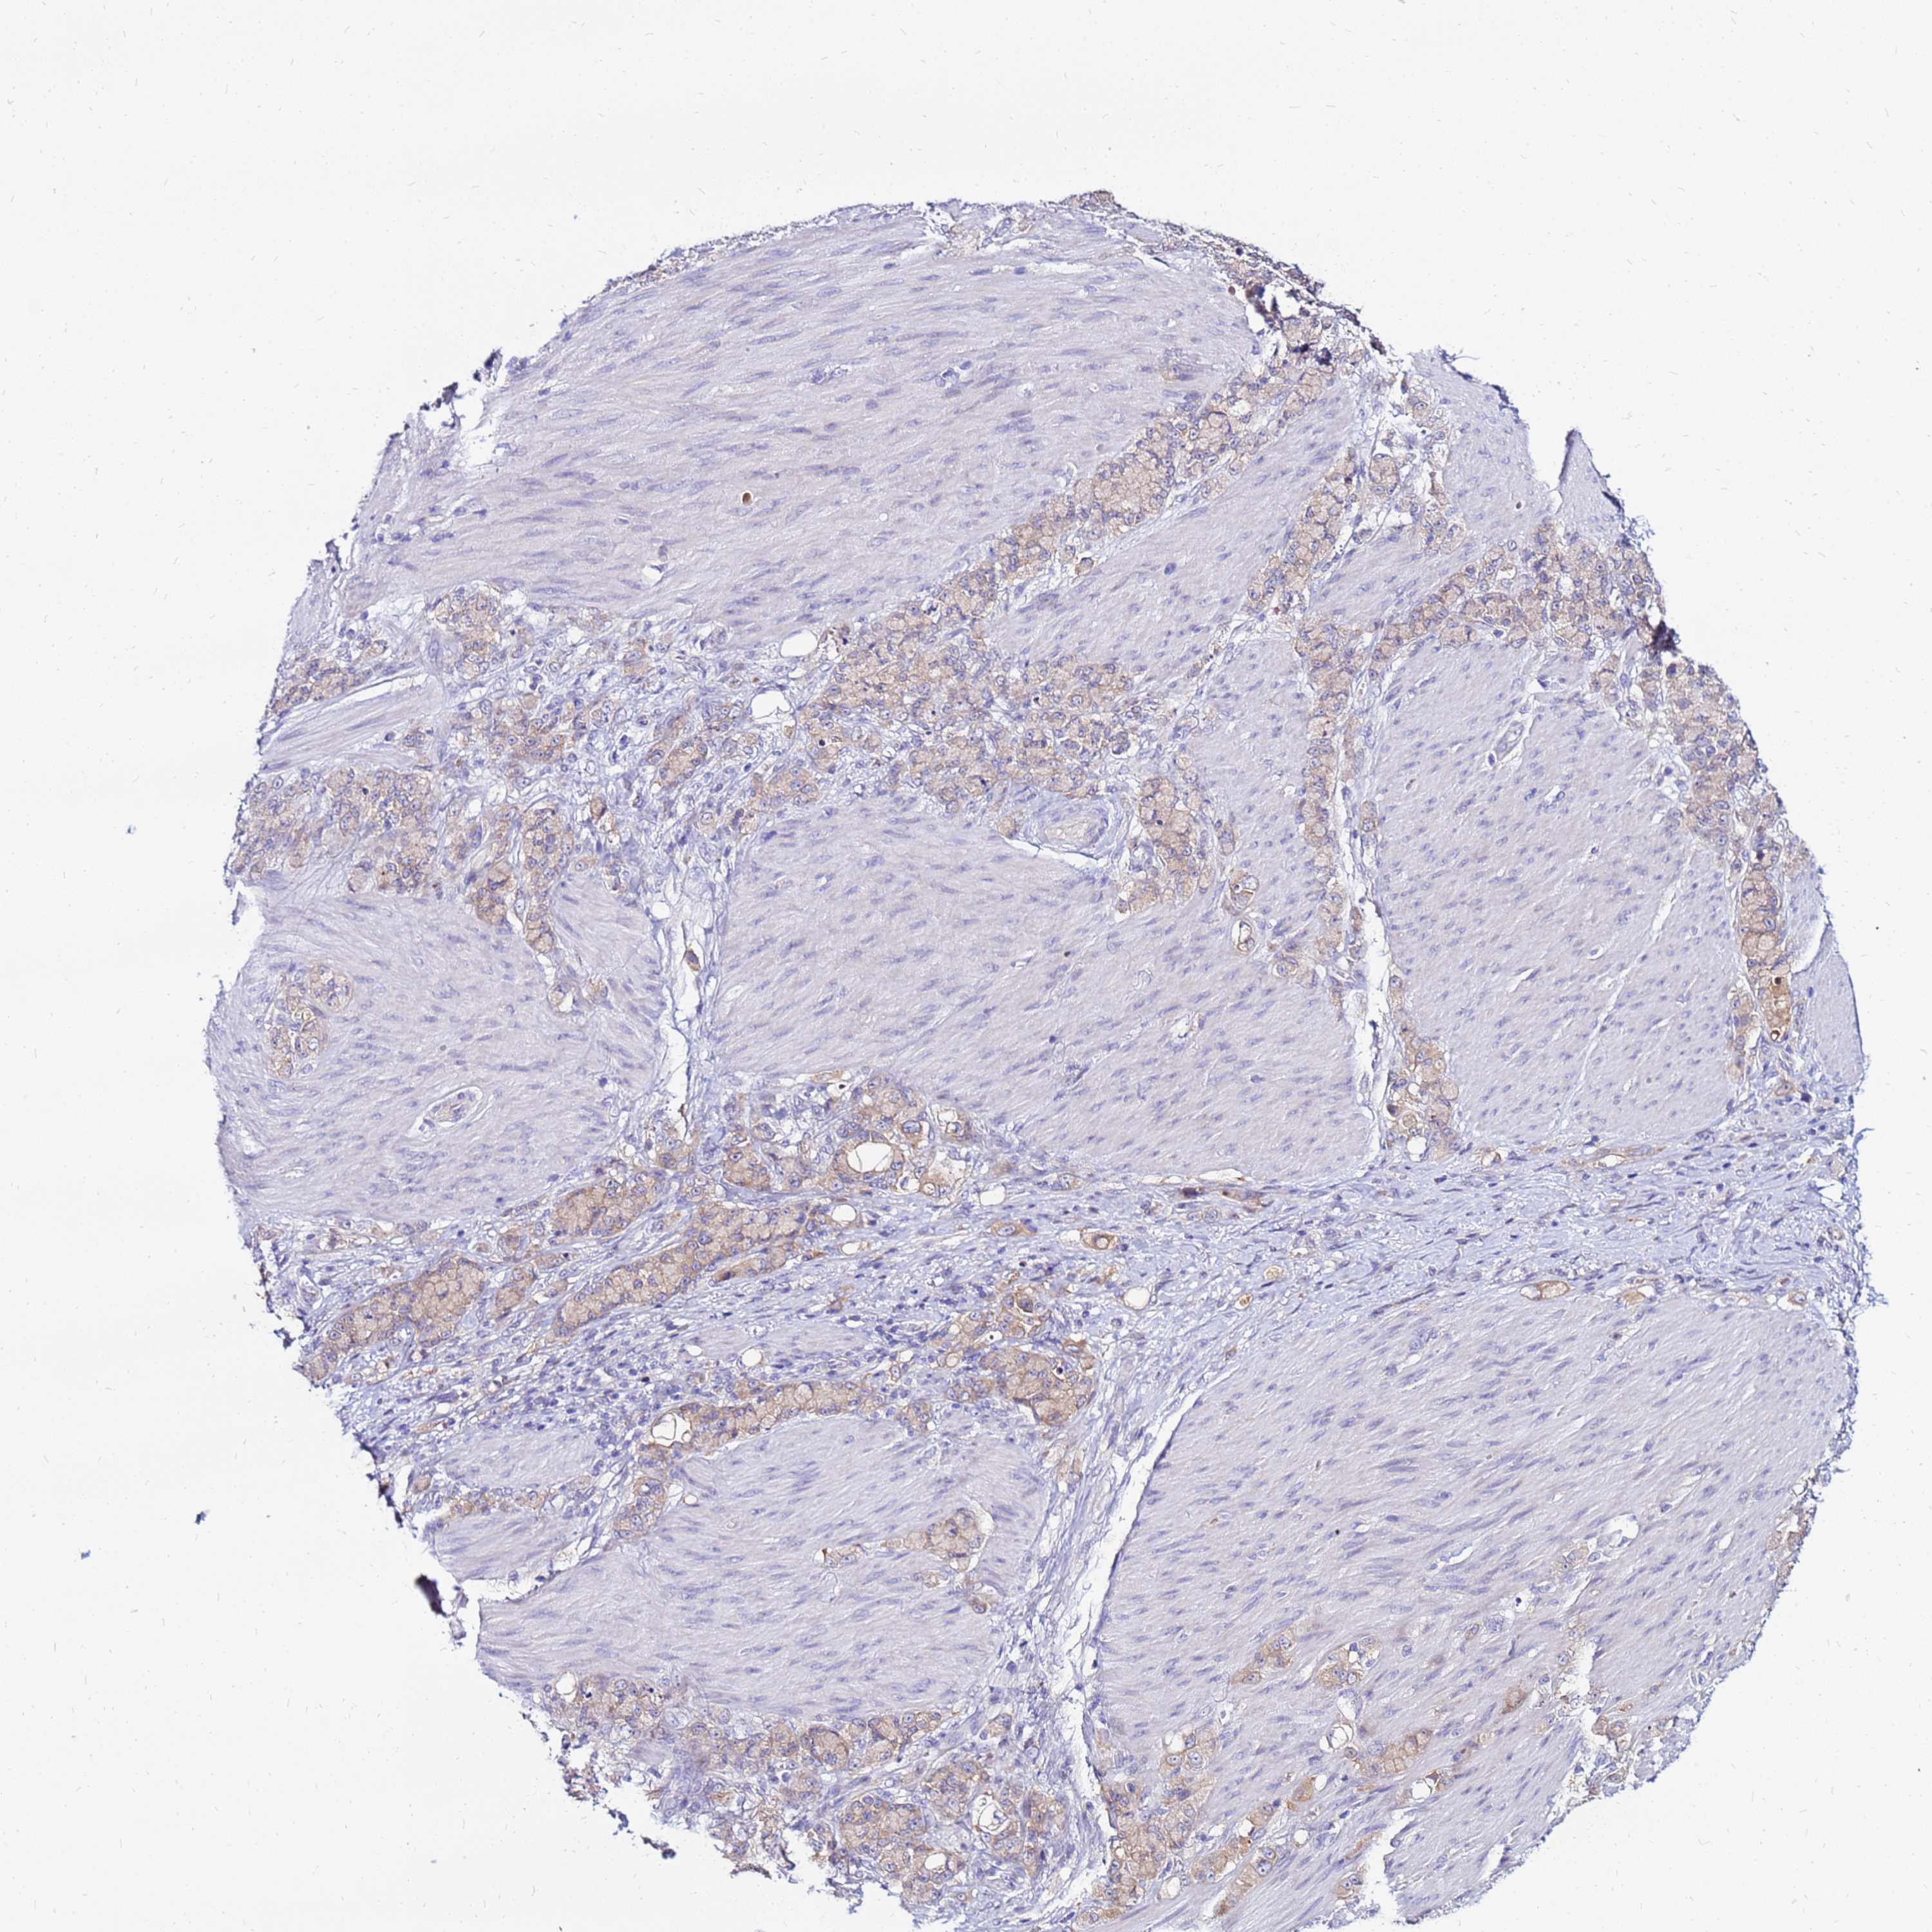

STOMACH CANCER - Protein expressioni

A mouse-over function shows sample information and annotation data. Click on an image to view it in a full screen mode. Samples can be filtered based on level of antibody staining by selecting one or several of the following categories: high, medium, low and not detected. The assay and annotation is described here.

Antibody stainingi

Antibody staining in the annotated cell types in the current human tissue is reported as not detected, low, medium, or high, based on conventional immunohistochemistry profiling in selected tissues. This score is based on the combination of the staining intensity and fraction of stained cells.

Each image is clickable and will lead to virtual microscopy that enables deeper exploration of all samples and also displays staining intensity scores, fraction scores and subcellular localization as well as patient and tissue information for each sample.

Antibody HPA044188

Antibody HPA045619

Antibody HPA045699

Staining

High

Medium

Low

Not detected

Intensity

Strong

Moderate

Weak

Negative

Quantity

>75%

75%-25%

<25%

None

Location

Nuclear

Cytoplasmic/membranous

Cytoplasmic/membranous,nuclear

Adenocarcinoma, NOS